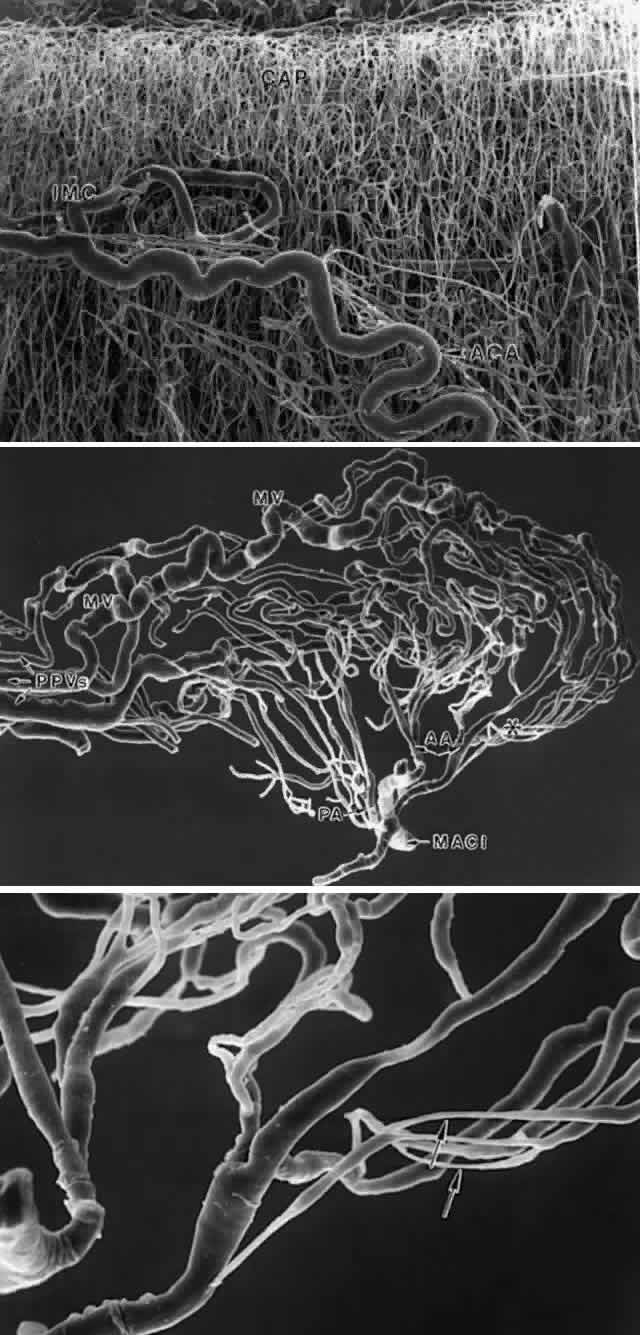

CILIARY BODY STROMA The stroma of the ciliary body contains all the usual components of extracellular

matrix including collagens, elastic system fibers, and small

matrix molecules such as proteoglycans. The cellular components are

melanocytes, fibroblasts, blood vessels, and nerves, besides the large

quantity of smooth muscle comprising the bulk of this tissue. In the

first one and one-half decades the nonvascular connective tissue in the

ciliary processes is scanty, resulting in the thin, underdeveloped appearance

of the juvenile ciliary processes (Fig. 28A). Their vessels are primarily fenestrated capillaries and veins, forming

plexi (see later section on blood supply). The subepithelial tissue

in the processes and plicae becomes very much thickened by collagenous

and hyaline material with aging (Fig. 28B and C), extending down to the ciliary muscle itself. In the deeper stroma, capillaries

are usually not fenestrated and show intermittent pericytes

outside the endothelial cell layer, surrounded by basement membrane that

merges with that of the endothelial cells (Fig. 29). The ciliary processes are essentially vascular structures and do not

contain extensions of the ciliary muscle, so the muscle has the same

The choriocapillaris does not continue forward into the ciliary body from

the choroid, but a thin layer of elastica continuous with Bruch's

membrane does (Fig. 31D). In the ciliary body, the elastica quickly becomes separated from the

basement membrane of the ciliary PE by the interposition of a dense and

then looser connective tissue (Fig. 31C). The elastic layer remains close to the underlying thin-walled pars plana

veins (Fig. 31A), becoming increasingly discontinuous (Fig. 31B) with wider branching, and is finally lost under the pars plicata.  Fig. 31. Bruch's membrane in the ciliary body. A. In mid pars plana, Bruch's

in traumatic hyphema. CILIARY MUSCLE The ciliary muscle has a complex architecture, and its three dimensional

organization and function have been difficult to visualize. Traditionally, the

muscle is divided into three portions (Fig. 34): an outer longitudinal or meridional portion ( Brücke's muscle), a

middle oblique portion (also called reticular or radial), and

an inner circular component ( Müller's muscle). These regions

are so interconnected that they were recognized early as designed to

function like a single muscle mass when stimulated.37 Experimental evidence in humans, primates, and other mammals supports

the view that the contracting ciliary muscle undergoes a shortening with

anterior traction on the ora serrata region, and an inward and posterior

pull on the scleral spur and trabeculum.6,38–40 Contraction of the oblique and circular portions in particular contributes

a strong anterior and inward movement of the processes. The result

is a well coordinated anterior-inward squeezing effect, displacing the

processes toward the lens equator, and resulting in relaxation of zonular

pull on the lens capsule. This inward movement of the ciliary processes

has been dramatically shown by cinematography in primates after

or myofibrils no longer anchored to their densities.54,55 THE ANTERIOR INSERTION OF THE CILIARY MUSCLE The possibility that the ciliary muscle fibers insert anteriorly in the

region of the scleral spur via “elastic tendons” was proposed

by Rohen several decades ago.37 He and his colleagues have made continual progress in understanding the

anterior muscle insertion and more recently the posterior insertion, adding

a new hypothesis about the cause of accommodative loss with aging. Three

types of anterior tendons are described.56 One attaches the tapering longitudinal muscle bundles to the anterior

sclera and scleral spur, and the second anchors in the trabecular meshwork. Both

consist of fibers described as elastic-like, showing extensive

connections to the elastic fibers of the scleral spur and the juxtacanalicular

elastic system (“cribriform plexus”56) as well as to the trabecular meshwork (Fig. 40). The fibers were called elastic-like because they do not resemble normal

elastic fibers and are not completely digested by elastase. Ultrastructurally

in the infant they contain a relatively small amount of elastin

in unfused cords with large numbers of elastic system microfibrils, like

an elaunin fiber (see Fig. 32D). However, the microfibrils become obscured by 50-nm granular banded “sheath” material by the second decade, and later an outer

layer of 100-nm banded material. This coating is reported to contain collagen

VI and chondroitin sulfate.57 The banded material increases markedly with age and in chronic open-angle

glaucoma. The origin of the third type of tendons is less clear, but

they are broad collagenous bands that cross the meshwork to insert

in the peripheral corneal stroma.  Fig. 40. Elastic fibers and insertion of anterior ciliary muscle. Tangential section

outflow complementary to that of the ciliary muscle.60 THE POSTERIOR ATTACHMENTS OF THE CILIARY MUSCLE The posterior attachments of the ciliary muscle have been studied extensively

in young and old primates (rhesus monkeys). Their elastic tendons

have many associated elastic microfibrils as in the anterior tendons, but

their elastin content is greater, with broader areas of more mature

fibers (Fig. 43A).62 The tendons have connections to the elastica surrounding the pars plana

vessels (Fig. 43B), and both have connections with the elastica of Bruch's membrane. These

elastic structures are connected to each other as well as to the

basement membranes of the ciliary epithelium and vascular walls by

oxytalan fibers (elastic microfibrils), so that the whole complex can

function as a unit.33,62,63 What percent of the tendons have direct attachments to Bruch's elastica

is still somewhat uncertain, as it is difficult to follow the elastic

fibers in their three-dimensional course, but the elastic network